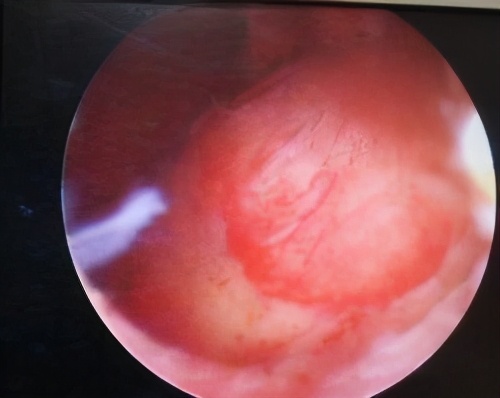

近日,科室收治了一名患者,该患者因月经淋漓不净伴阴道不规则流血,中度贫血,彩超提示宫腔内不均、质低回声团,大小约4.5x5.0cm大小。患者在外院就诊咨询后,建议行子宫全切,患者抱着保留子宫的愿望来到我院妇科,因患者肌瘤较大(一般宫腔镜下肌瘤挖除,建议肌瘤不超过3cm)。患者肌瘤较大,手术难度较高,但患者保留子宫的意愿非常强烈。结合患者基本情况,管床医生和科室业务⻣干反复讨论后拟定了患者的手术方案,于6月118日在静脉麻醉下完整进行了肌瘤摘除。手术时间短,创面小,术后基本无流血,病人恢复良好。